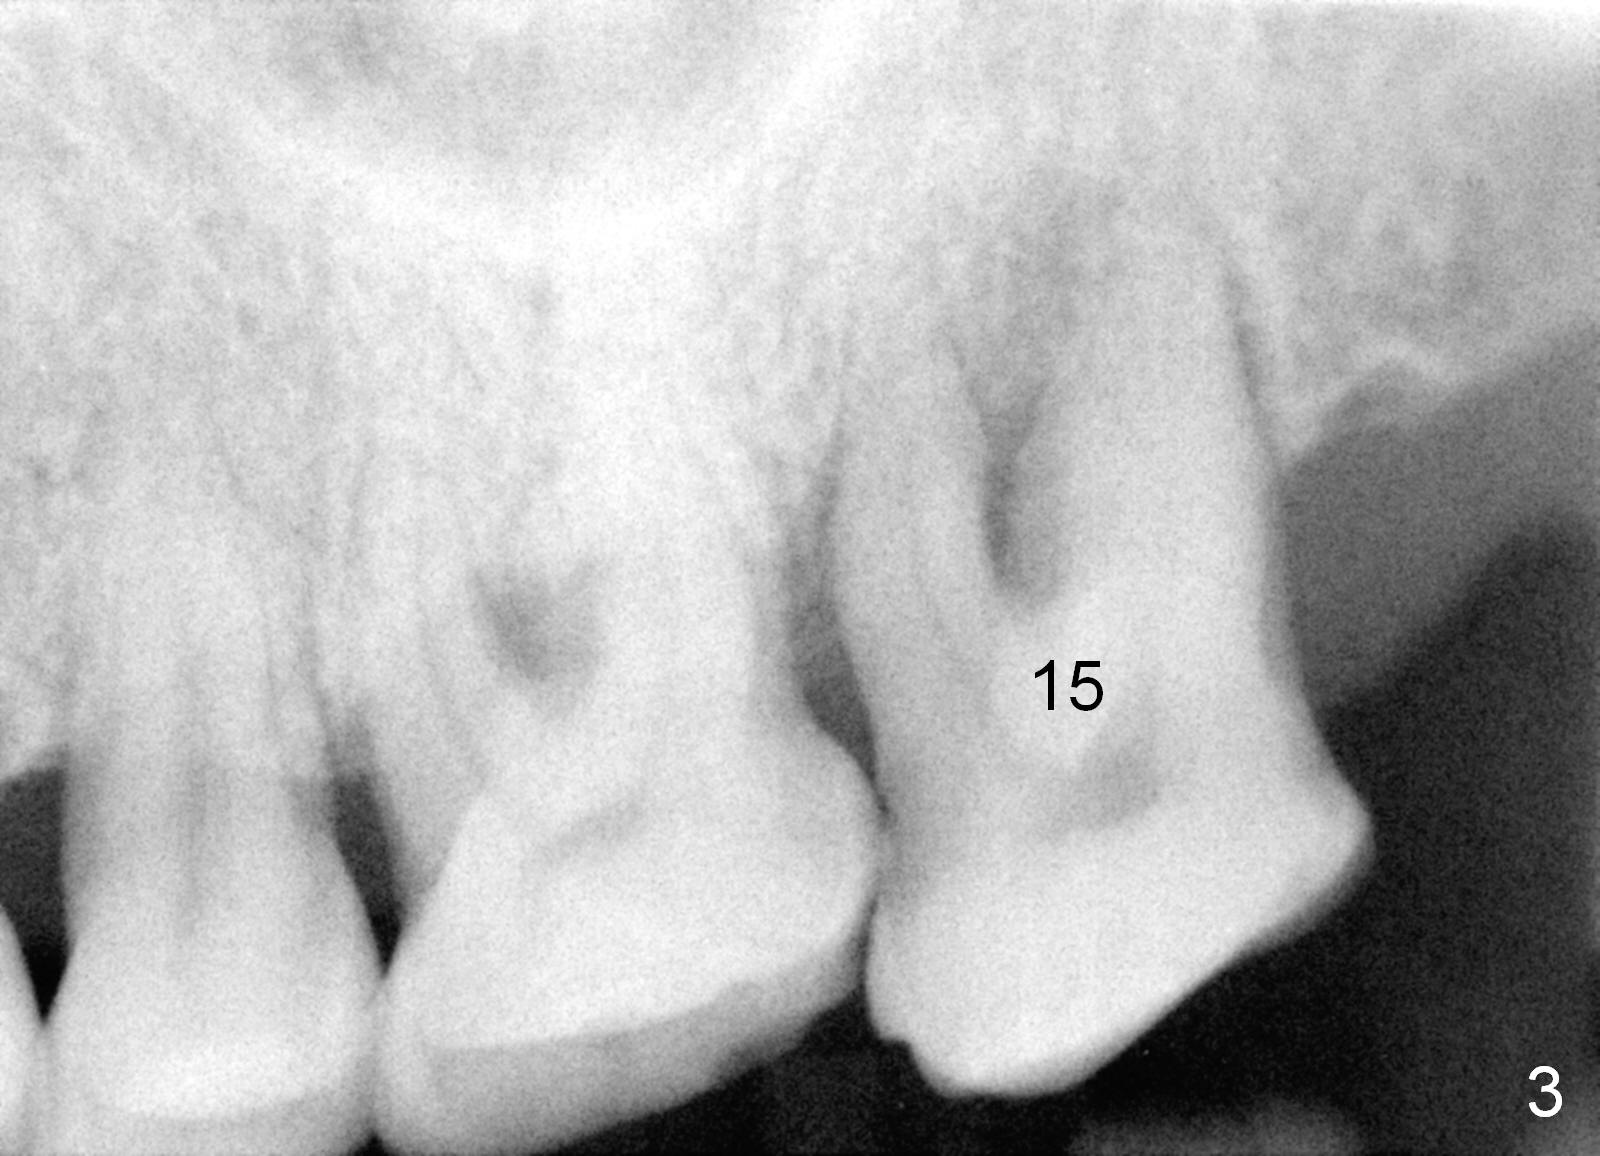

A 53-year-old man (ZB) has history of chronic periodontitis and bruxism. The tooth #18 has been extracted for a few years, while the tooth #15 is going to (Fig.1). Bone height for #15 immediate implant is not a problem (Fig.2-4; green line in Fig.2: sinus floor). After extraction (Fig.5 )socket to be treated with Clindamycin), use starter drill and a 2 mm pilot drill with stopper at 10 mm (Fig.6) on the crest of the septum (Fig.5 S). PA is taken with a parallel pin. Adjust the length accordingly. Subsequent osteotomy will be carried out with drills with stopper at 50 RPM. In brief, the implant does not need to be large. It should be placed as deep as possible (1-2 mm subcrestal mesially and/or distally), since the vertical height in the posterior region is limited. The margin of a cemented abutment is to be slightly subgingival. Use an immediate provisional to close socket gap, while to keep abutment margin from the gingiva. Use Collagen dressing before and after bone graft.